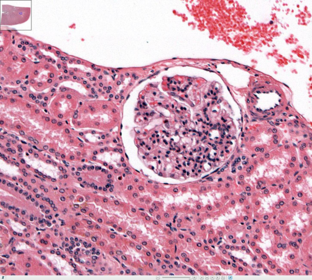

What type of tissue surrounds the glomerulus of the kidney? What about away from it? (spaghetti and meat balls) Simple squamous epithelium simple cuboidal epithelium